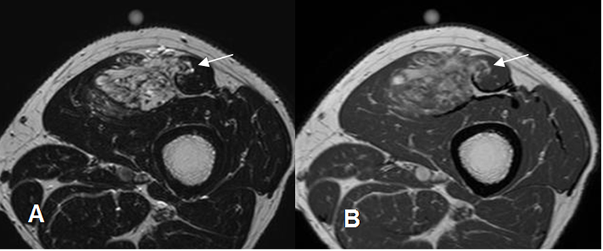

Fig 48. Estadiaje.

A: RM axial en T2 y B: RM axial en T1 con contraste. Histiocitoma fibroso maligno del recto anterior, que se extiende al músculo sartorio.